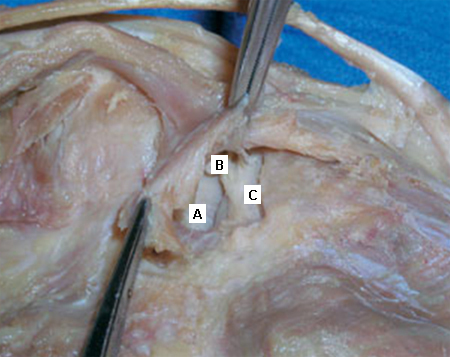

Deep dissection of the posteromedial capsule. The two expansions of the semimembranosus muscle have been elevated, exposing the weak area of the capsule between the posterior cruciate ligament (A) and the posterior horn of the medial meniscus (B) that gives entry to the knee joint. The medial femoral condyle is also visible (C)

Adapted from Labropoulos N, Shifrin DA, Paxinos O. New insights into the development of popliteal cysts. Br J Surg. 2004;91:1313-1318; used with permission